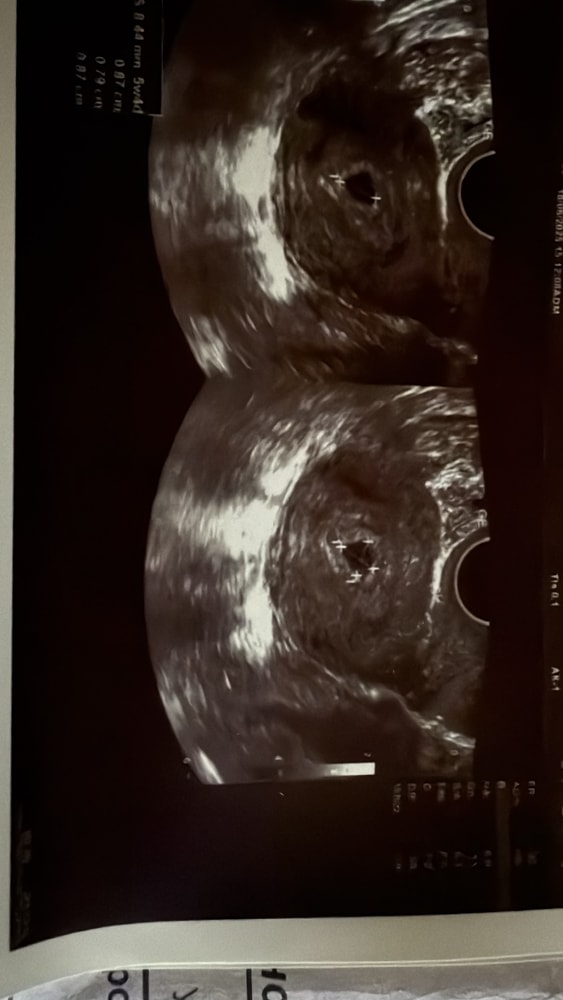

УЗИ 18 дпп

Сегодня перепугалась , стал сильно каменный живот и очень тянул , пошла на узи , сейчас все вложу , в голове куча переживаний …. Скажите пожалуйста на какой день дпп у вас увидели эмбрион ? Хгч был на 16 дпп -6500

Подскажите вам Ре ничего на счёт желточного мешочка не сказала? Просто вопрос стоит рядом с размером

Узистка сказала , маленький срок еще